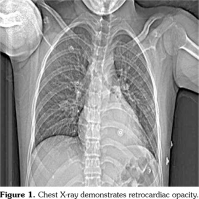

Chest X-ray showed retrocardiac hyperdensity on admission (Figure 1). Diagnostic investigations for tuberculosis were all negative. On bronchoscopy; left lower lobe bronchus was narrowed due to the external compression and abundant viscous secretions were observed. Computed tomography (CT) angiography was performed, which was consistent with multiple PAAs bilaterally (Figure 2). Diagnostic investigations such as echocardiogram and lower extremity venous Doppler ultrasonography, renal function evaluation, eye examination, abdominal ultrasound, and rheumatologic tests revealed no pathological findings. Our patient’s investigational tests for PAA were negative for cardiovascular disease, pulmonary hypertension or any infection.